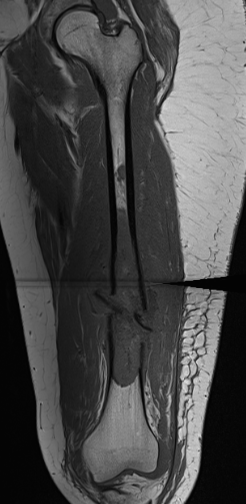

MRI

Low signal intensity of T1 / high signal intensity on T2

- intramedullary extent

- skip lesions

Significant soft tissue mass with significant edema

Pathological fracture with skip lesion

Ewing's femoral diaphysis, subtle on xray with large soft tissue component